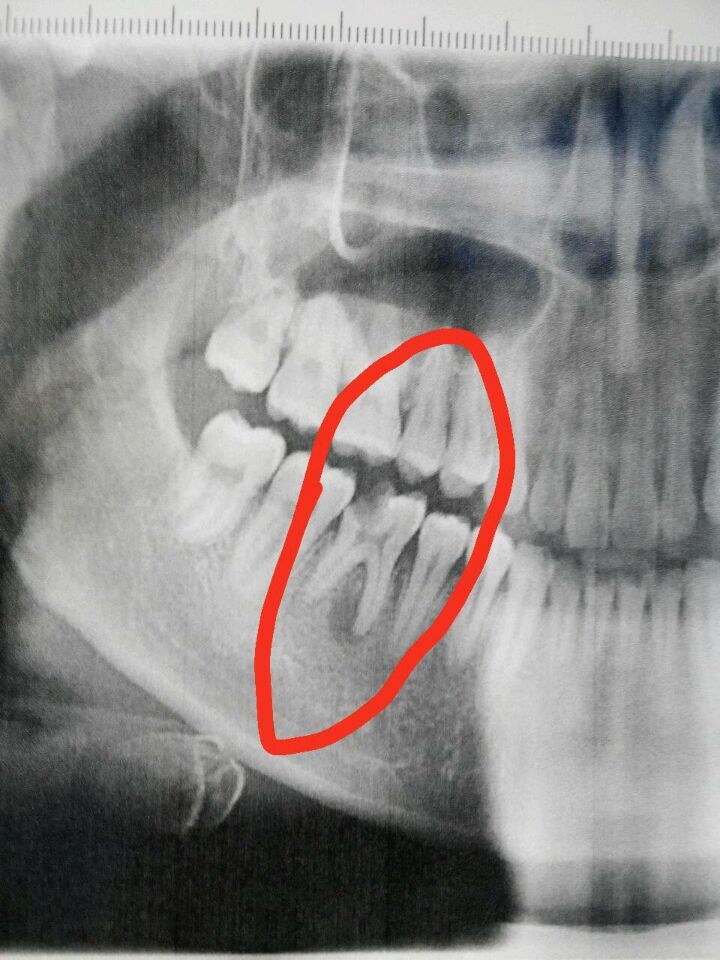

牙齒蛀牙拍片